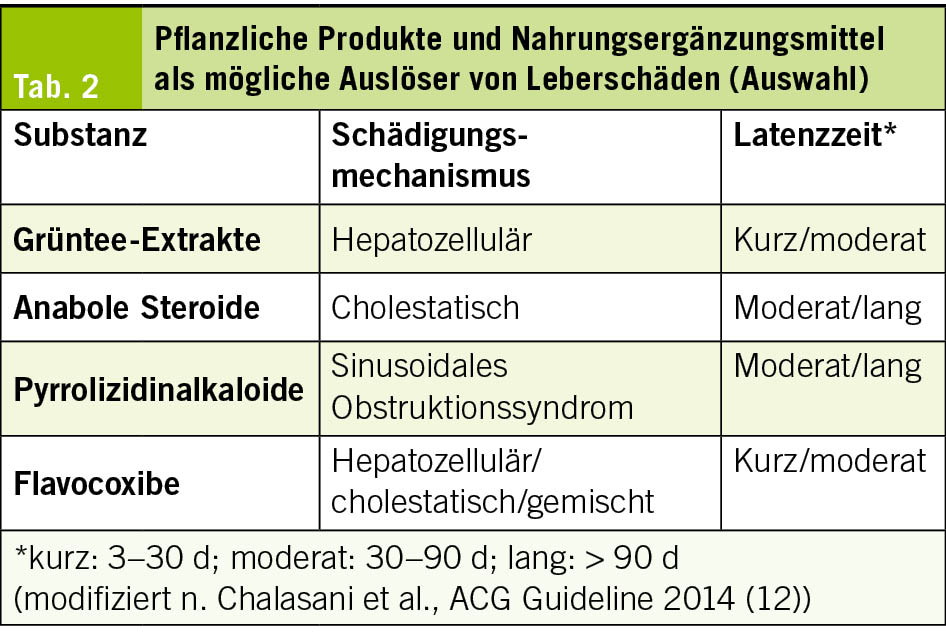

Auch pflanzliche Produkte und Nahrungsergänzungsmittel (Herbal and Dietary Supplements, HDS) konnten als Ursache von DILI identifiziert werden. In den westlichen Ländern wurde ein deutlicher Anstieg HDS-assoziierter Leberschäden beschrieben. Nach Daten eines US-amerikanischen DILI-Registers entfallen etwa 16 % der medikamentös-toxischen Leberschäden auf HDS, während in ostasiatischen Ländern wie China, Korea und Singapur der Anteil auf 27–62 % aller DILI-Fälle geschätzt wird. Diese Präparate werden häufig zur Gewichtsreduktion, Leistungssteigerung oder allgemeinen Gesundheitsförderung eingenommen und nicht immer als relevante Medikation wahrgenommen.

Für die Diagnostik ist eine gezielte Anamnese essenziell. Neben dem Produktnamen sollten Beginn und Dauer der Einnahme, Dosierung, Bezugsquelle sowie die gleichzeitige Einnahme weiterer Präparate erfasst werden. Viele Produkte enthalten mehrere pharmakologisch aktive Substanzen oder sind mit nicht deklarierten Inhaltsstoffen kontaminiert. Da HDS häufig nicht als «Medikamente» wahrgenommen werden, werden sie anamnestisch oft nicht spontan angegeben. Hilfreich kann es sein, Patienten zu bitten, die Präparate oder entsprechende Fotos mitzubringen. Typische Produkte sind in Tab. 2 zusammengefasst. Aktuell sind mehr als 100 Substanzen mit hepatotoxischen Wirkungen beschrieben. Zu den häufigsten Auslösern zählen anabole Steroide, Grüntee-Extrakte sowie Kombinationspräparate zur Gewichtsreduktion. Insbesondere bei pflanzlichen Mischungen ist die Identifikation der verantwortlichen Substanz schwierig. Für einzelne Stoffe bestehen jedoch charakteristische Schädigungsmuster, etwa ein prolongierter, meist selbstlimitierender Ikterus bei anabolen Steroiden oder ein sinusoidales Obstruktionssyndrom durch Pyrrolizidinalkaloide aus der traditionellen chinesischen Medizin. Die Mehrzahl der Substanzen manifestiert sich als unspezifische akute Hepatitis. Eine Übersicht potenziell hepatotoxischer Substanzen ist in der Datenbank LiverTox verfügbar (www.ncbi.nlm.nih.gov/books/NBK547852/).

Das Absetzen führt meist zur Erholung, schwere Verläufe bis hin zum akuten Leberversagen sind jedoch beschrieben (12, 20, 21).